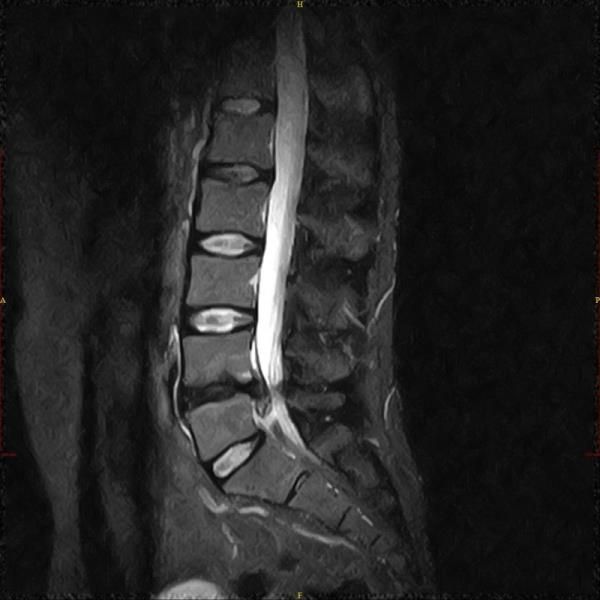

Beim akuten wie auch beim chronischen Bandscheibenvorfall werden entzündungshemmende Medikamente in die unmittelbare Nähe des Bandscheibenvorfalls und des Entzündungsprozesses injiziert. Die Entzündung klingt ab und die Schwellung wird geringer.

Daher bedarf der Bandscheibenvorfall heute nur selten einer klassischen Operation, um ihn erfolgreich zu behandeln und Schmerzfreiheit zu erreichen. Im Gegenteil, da nach Operationen die Gefahr von Verwachsungen und damit verbundenen oft lang anhaltenden starken Beschwerden recht hoch ist, sollte ein operativer Eingriff nur bei Lähmungserscheinungen oder bei nicht durch konservative Therapie zu bessernde Beschwerden in Erwägung gezogen werden.